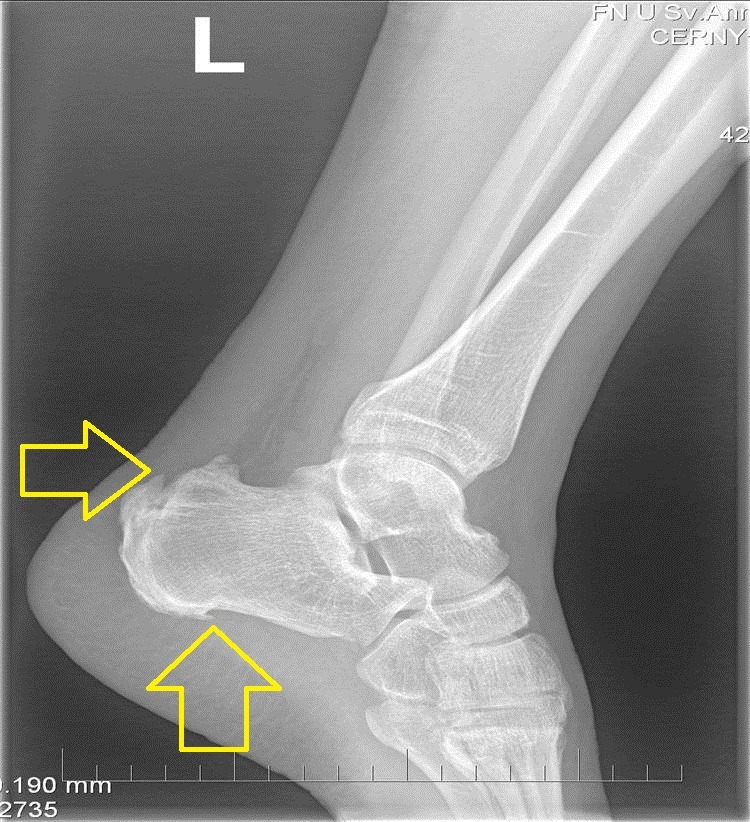

Příčiny:

- Opakované mechanické dráždění: Nejčastěji způsobené nošením těsné obuvi s tvrdým opatkem, který tlačí na patu.

- Tvar nohy: Lidé s vysokou klenbou nebo s výraznějším sklonem patní kosti jsou náchylnější.

- Sportovní aktivity: Zejména běh, bruslení nebo sporty s častými doskoky.

Příznaky:

- Bolest na zadní straně paty, zejména při chůzi, běhu nebo tlaku na postižené místo.

- Otok a zarudnutí v oblasti paty.

- Kostní výrůstek, který může být viditelný a hmatatelný.

- Otlaky a puchýře způsobené třením obuvi.

Diagnostika:

- Fyzikální vyšetření: Lékař prohmatá patu a zhodnotí příznaky.

- Rentgenové vyšetření: Potvrdí přítomnost kostního výrůstku.

- Ultrazvuk nebo magnetická rezonance: Mohou být použity k posouzení stavu Achillovy šlachy a okolních měkkých tkání.